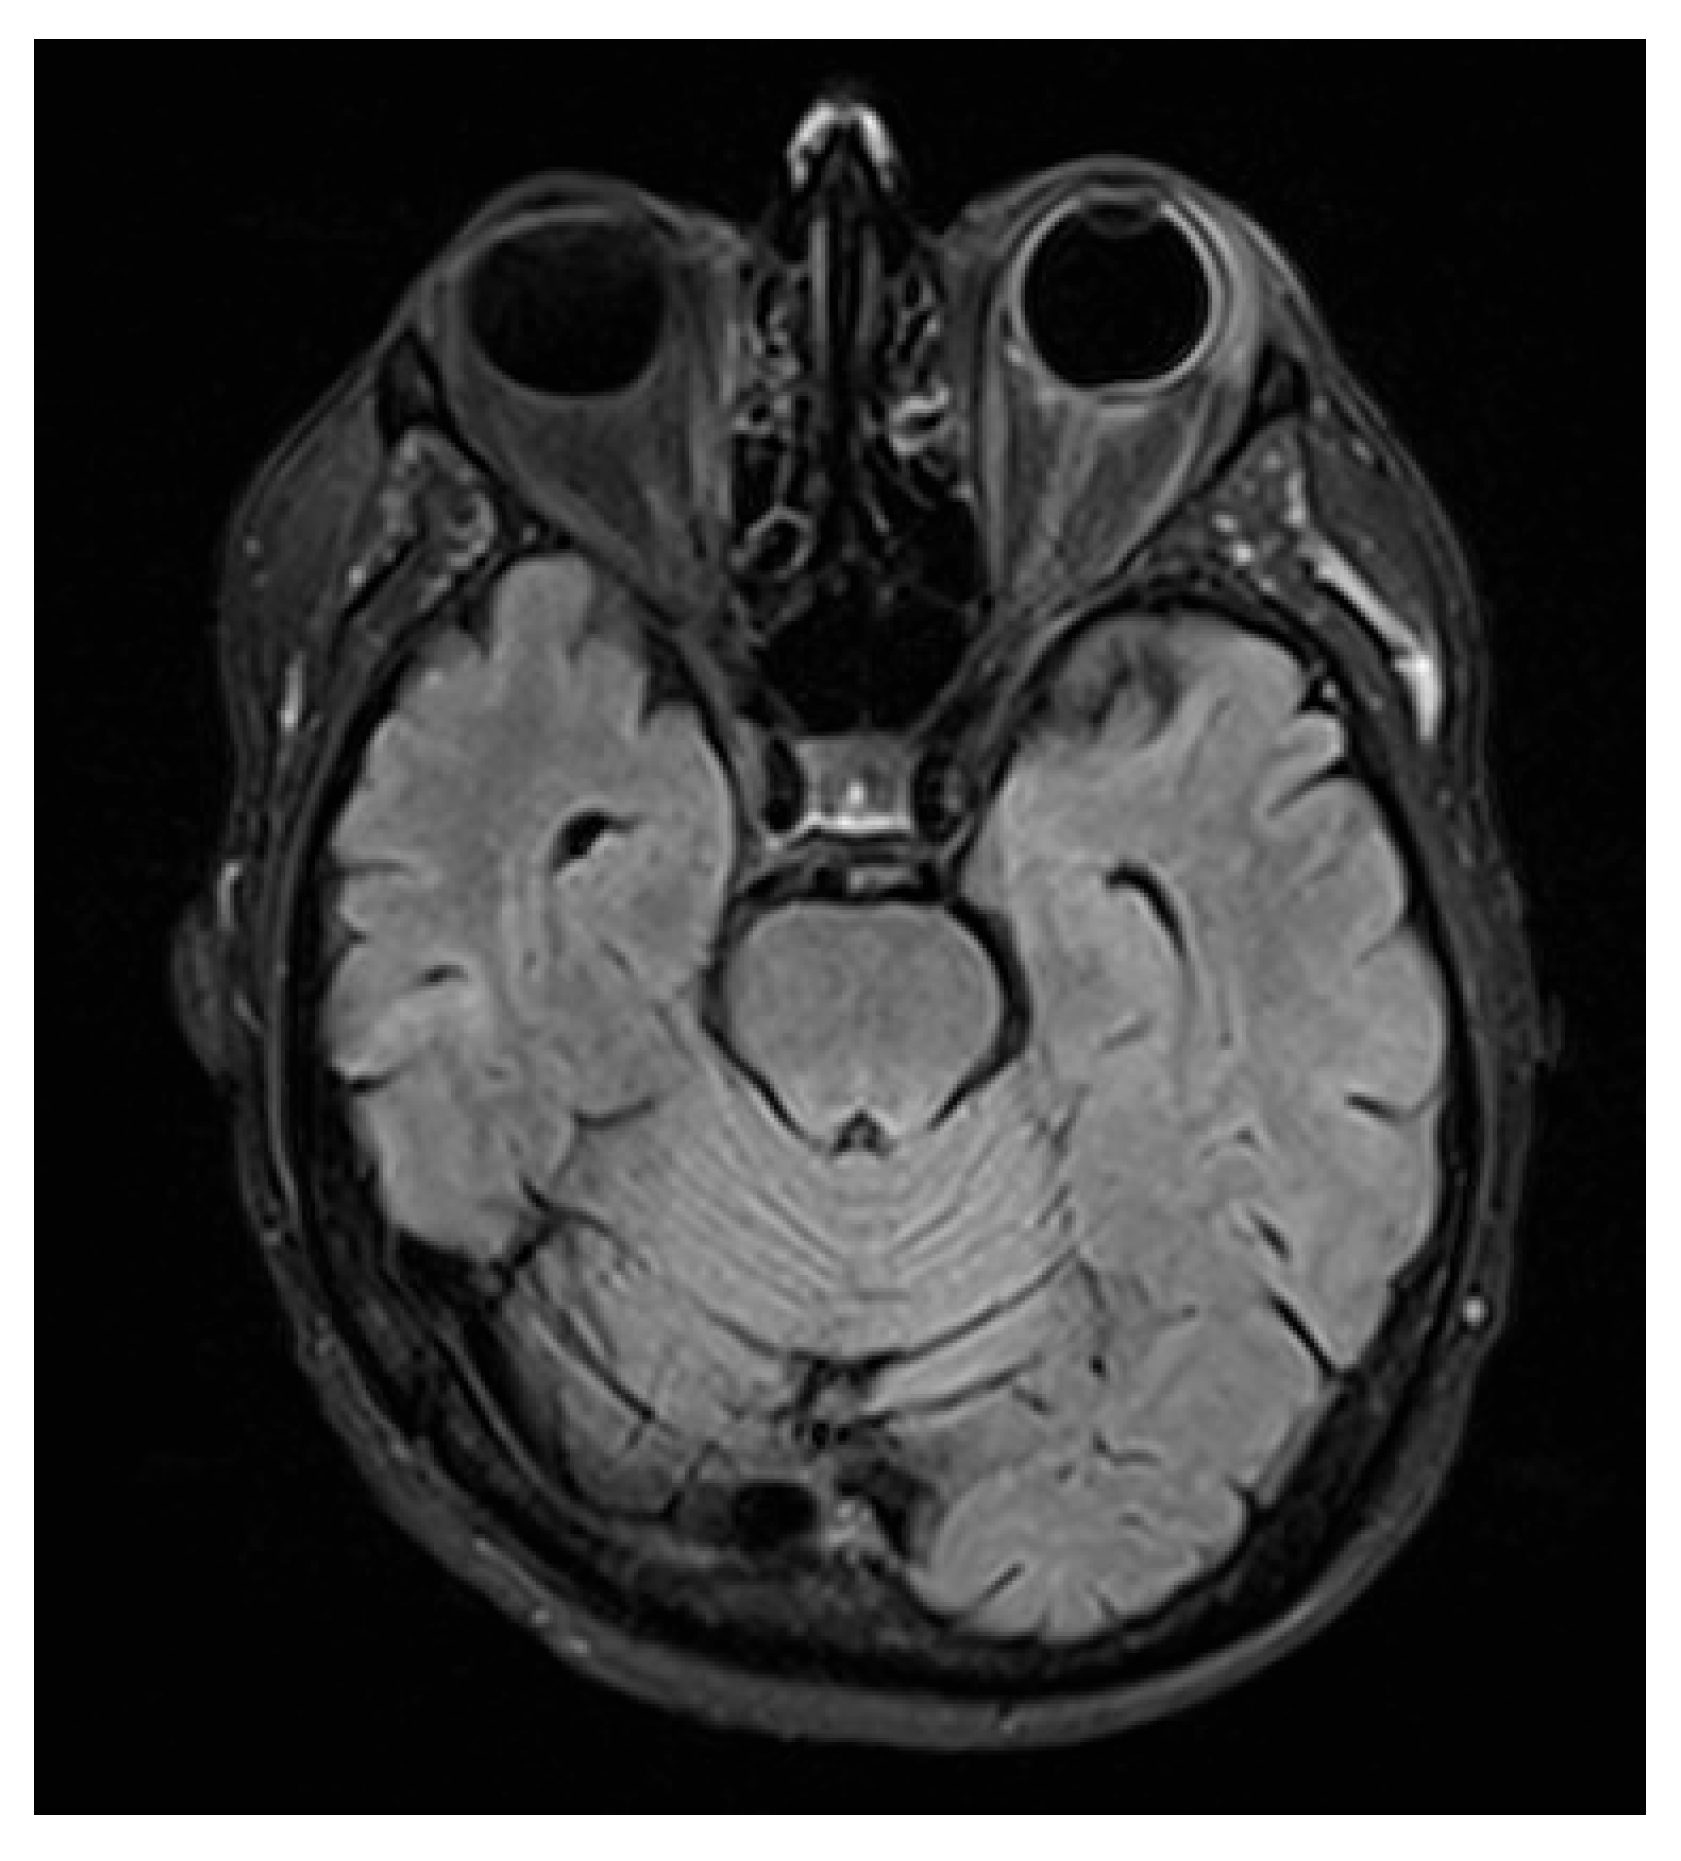

MRI of the brain and orbits was obtained. Neuroimaging demonstrated minute, focal hypointense lesions in both supratentorial and infratentorial regions, compatible with microbleeds, without signal abnormalities suggestive of CNS leukemic localization.

Figure 2. Orbital MRI (T2-FLAIR) showing hyperintensity of the retro- and periorbital fat, posterior sclera, and optic nerve sheath, consistent with leukemic infiltration extending to adnexal and retrobulbar tissues.